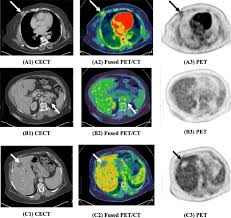

Can Ct Scan With Contrast Detect Breast Cancer - Breast Lumps Diagnosis Evaluation And Treatment : The cancer develops when abnormal cells crowd out healthy ones, potentially causing a lump in the breast or a bloody discharge from the nipples.. Breast cancer affects over 200,000 women each year. Luckily, i was still diagnosed pretty early. A ct scan is also called computerized axial tomography (cat) scan. In contrast with bone scans, which are only able to detect bone metastases, pet/ct has the advantage of concurrently imaging other common sites of breast cancer metastases such as the liver and lungs, says lead author patrick morris, a breast cancer specialist at memorial sloan kettering. This is an excellent way to take a needle biopsy for inflammatory breast cancer because imaging can show the best place to take the biopsy.

Learn the stage of your cancer. The term tomography comes from the greek words tomos (a cut, a slice, or a section) and graphein (to write or record). In contrast with bone scans, which are only able to detect bone metastases, pet/ct has the advantage of concurrently imaging other common sites of breast cancer metastases such as the liver and lungs, says lead author patrick morris, a breast cancer specialist at memorial sloan kettering. This is an excellent way to take a needle biopsy for inflammatory breast cancer because imaging can show the best place to take the biopsy. Ct scans are most often done as an outpatient procedure.

Before a pet/ct scan, an iv that injects a small amount of a radioactive substance will be placed into one of your veins. It also helps doctors predict how well you will recover.find the right place for a biopsy.plan A pelvic ct scan can be used to detect several types of cancer. When the doctor knows this, they can choose the best course of treatment and maybe even predict your chances of recovery. The scan lets them:learn the cancer's stage. However, they are also scanning my thorax. I performed an scope examination of her esophagus and confronted a huge cancer occupying the lower portion of her esophagus. A ct scan can help detect a wide range of abnormalities or disease, including cancer, in any part of the body. Each picture created during a ct procedure. Further, its diagnostic reach can go beyond the bone. You are encouraged to drink clear liquids. Do ct scans detect breast cancer? Learn more about it on our blog.

Ct scans can help doctors: If you have a large breast cancer, your doctor may order a ct scan to assess whether or not the cancer has moved into the chest wall. This substance is often called a tracer, because it helps reveal cancer in the body. The scan lets them:learn the cancer's stage. Computed tomography scan, ct scan, cat scan, and spiral or helical ct. 234 views answered >2 years ago Before the scan, you will either drink a liquid dye or be given an injection of dye into a vein in your arm. Breast cancer affects over 200,000 women each year. A pelvic ct scan can be used to detect several types of cancer. Contrast medium is a dye that helps body tissues show up more clearly on the scan. In contrast with bone scans, which are only able to detect bone metastases, pet/ct has the advantage of concurrently imaging other common sites of breast cancer metastases such as the liver and lungs, says lead author patrick morris, a breast cancer specialist at memorial sloan kettering. You are encouraged to drink clear liquids. This helps determine whether or not the cancer can be removed with mastectomy.